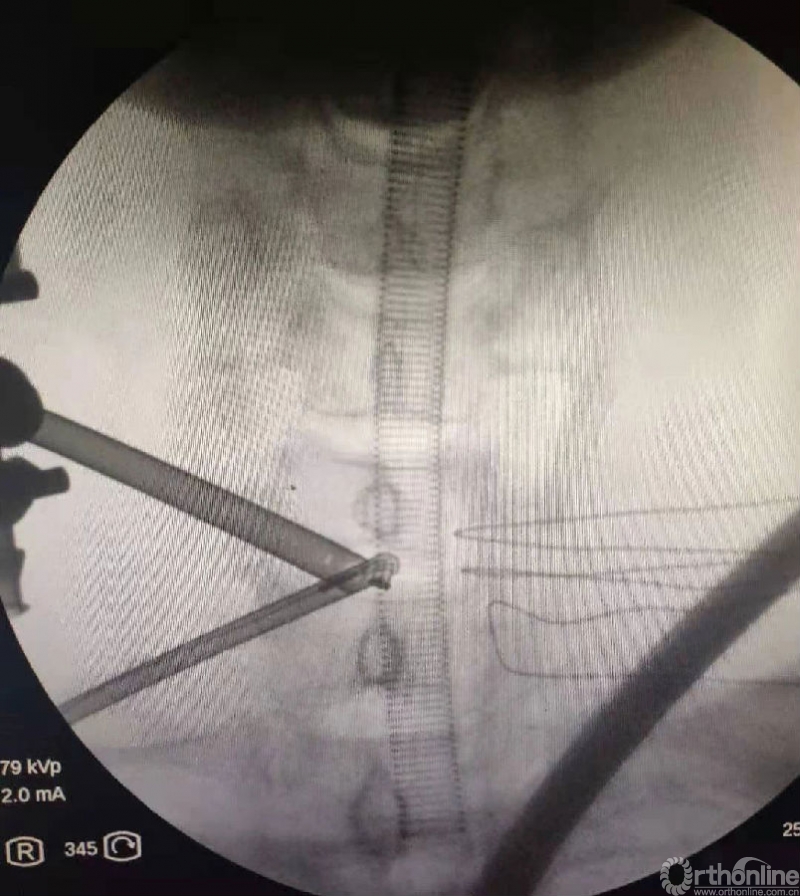

以颈椎为例

颈椎ULBD单侧入路双侧减压减压的难点还是在于识别棘突与椎板的移行部位及对侧结构的显露。

0度镜子绝对是颈椎UBE的最好用的镜子,但是30度的镜子对侧中线结构的显露及对侧结构的显露具有更广角的视野。在进行同侧减压之前,中线结构的显露是关键。

以C6/7节段病例为例,中线结构的区域解剖如下: